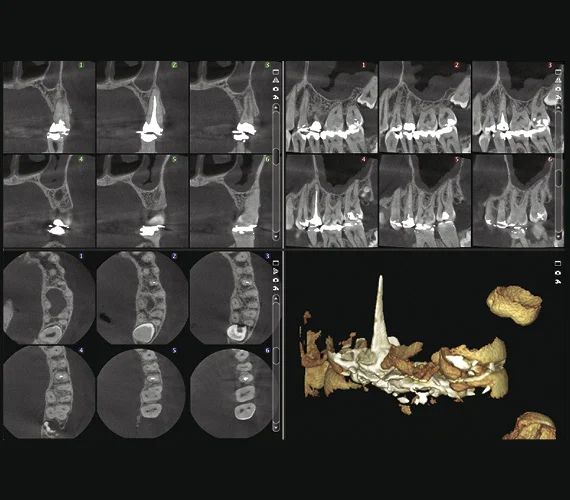

Качество изображения — клинические изображения

Специальный эндодонтический режим визуализации

Качество изображения имеет большое значение, но состоит из мелочей. Эндодонтический режим визуализации идеально подходит для съемки мелких анатомических деталей. Он предлагает исключительно высокое разрешение с размером вокселя 75 мкм.